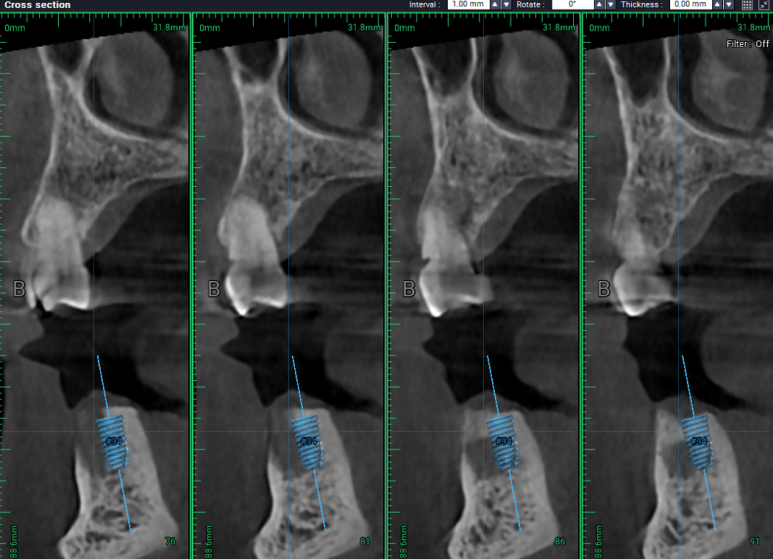

#34,36,37 자리에 임플란트를 식립할 예정이었어요.

#34번 부위는 임플란트를 위치시키고 나면 협측으로 뼈이식을 반드시 넉넉하게 해야할 모양새였습니다.

비교적 뽑은지 오래되었던 #36,37 치아는 잇몸뼈가 넉넉하게 보였습니다.

두 큰어금니 부위는 하치조신경관(아래이틀신경)만 조심해서 적절한 임플란트를 심어놓으면 되었습니다.